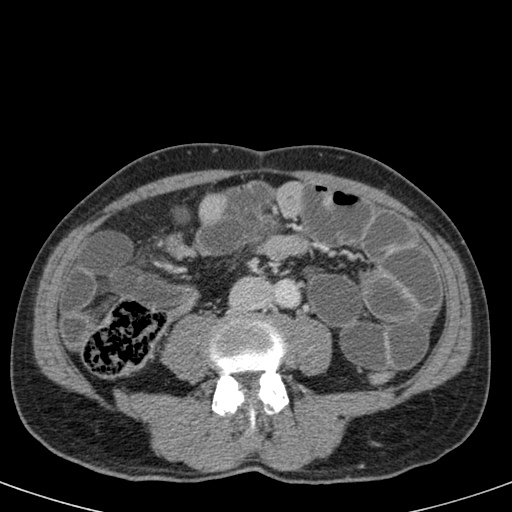

Ca lâm sàng bên trái cho thấy một bệnh nhân khác bị tắc ruột dạng quai kín.

Mặc dù các mạch máu ngấm thuốc tốt, nhưng dường như thành ruột không ngấm thuốc.

Các dấu hiệu thiếu máu cục bộ khác trong ca này bao gồm phù nề mạc treo và dày thành ruột.

Ruột bị nhồi máu được phát hiện trong quá trình phẫu thuật.

Nếu quai kín dài hơn và định hướng vuông góc với mặt phẳng cắt, chúng ta sẽ thấy một cụm quai ruột như trong ca lâm sàng bên trái.

Đôi khi điều này khó nhận biết chỉ trên các lát cắt ngang và các tái tạo mặt phẳng coronal hoặc sagittal có thể hữu ích.

Trong ca này, cũng có phù nề mạc treo và cổ